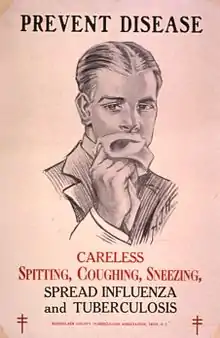

Public health

Public health campaigns which have focused on overcrowding, public spitting and regular sanitation (including hand washing) during the 1800s helped to either interrupt or slow spread which when combined with contact tracing, isolation and treatment helped to dramatically curb the transmission of both tuberculosis and other airborne diseases which led to the elimination of tuberculosis as a major public health issue in most developed economies.[91][92] Other risk factors which worsened TB spread such as malnutrition were also ameliorated, but since the emergence of HIV a new population of immunocompromised individuals was available for TB to infect.